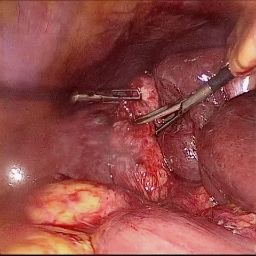

Refer to caption (a) Input Refer to caption (b) case1 Refer to caption (c) case2 Refer to caption (d) case3 Refer to caption (e) Ours Refer to caption (f) Target

Figure 4: Ablation comparisons sampled from the DesmokeData and LSD3K datasets. The first two rows are from DesmokeData and the last two rows are from LSD3K. (settings: case1 = ADA+CrossGating, case2 = DHA+CrossGating, case3 = DHA+ADA).

IV-D Ablation Studies

To validate the effectiveness and individual contributions of the core components of our proposed RGA-Net, we conducted a series of ablation experiments on the DesmokeData dataset. We systematically analyzed the impact of our key designs: the DHA module, the ADA module, and the Cross-Gating (CG) mechanism for feature fusion. In these studies, we created several variants of our network by removing or replacing one component at a time and evaluated their performance. The quantitative results of these experiments are presented in Table II, and qualitative visual comparisons are shown in Fig. 4.

IV-D1 Effectiveness of the Dual-Stream Hybrid Attention Module

The DHA module is designed to capture both local surgical details and global illumination changes by combining shifted window attention with a frequency-domain processing branch. To ablate its effect, we replaced the DHA modules in the encoder with standard Swin Transformer blocks, thus removing the spectral pathway and the hybrid attention mechanism. As demonstrated in Table II, this variant experienced a significant drop in performance. This decline highlights the importance of integrating frequency-domain information, which is crucial for handling the complex light scattering caused by surgical smoke and restoring high-frequency textural details. The results confirm that the dual-stream approach provides a richer feature representation than spatial attention alone.

IV-D2 Effectiveness of the Axis-Decomposed Attention Module

We then investigated the contribution of the ADA module, which is employed in the decoder and latent space to efficiently process multi-scale features. We created a variant where the ADA modules were substituted with a more conventional self-attention mechanism without the block and grid axis decomposition. The results in Table II show a clear degradation in performance for this variant compared to the full model. This outcome validates that factorizing attention along two distinct axes allows the model to capture both fine-grained local patterns and long-range spatial dependencies more effectively and efficiently. The ADA module’s design provides a powerful yet computationally manageable way to model complex feature relationships during the reconstruction phase.

IV-D3 Effectiveness of the Cross-Gating Mechanism

Finally, we analyzed the efficacy of the cross-gating mechanism used for multi-scale feature fusion between the encoder and decoder. We replaced our CG blocks with a standard skip-connection method, specifically simple concatenation followed by a convolutional layer, as is common in many U-Net-based architectures. As shown in Table II, this change resulted in a substantial performance decrease. This finding underscores the superiority of the bidirectional feature modulation offered by our CG mechanism. Unlike simple fusion, cross-gating allows the encoder and decoder pathways to selectively amplify relevant features and suppress irrelevant information from each other, leading to a more refined and effective integration of multi-scale context, which is vital for high-quality image reconstruction.

In conclusion, the ablation studies comprehensively demonstrate that each of our proposed components—DHA, ADA, and CG—is integral to the overall performance of RGA-Net. The full model consistently outperforms all ablated variants, proving the synergistic benefits of our architectural design for the challenging task of surgical smoke removal.